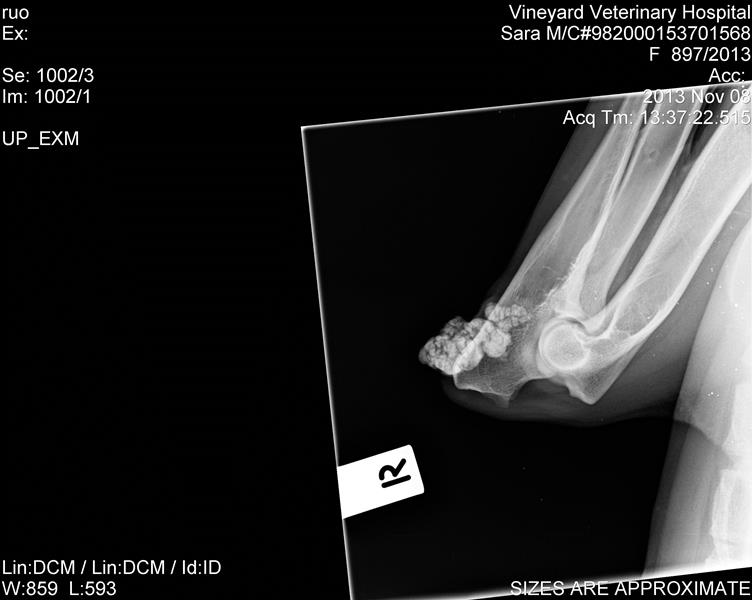

I had some feedback from someone i emailed with the scans, they look pretty good, was the comment.

"Her hips and elbows are fairly good. The hips - the right hip is just slightly shallow and just slightly loose - nothing to worry about, the left hip has a very slight thickening of the cranial acetabular edge, again nothing to worry about, her elbows are normal. There is a calcinosis ( calcium deposit next to one elbow - again not an issue, won't cause any lameness etc.

Her hips would probably score around 6-8 on the right and 4-5 on the left. The pass mark for the "A" stamp is a maximum of 8 points in total with no more than 3 points in any one area. Certainly would not be concerned about either of her hips or elbows as a long term issue,"